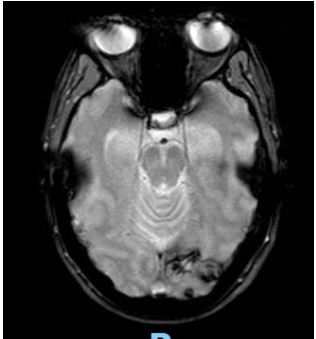

Posteriormente se solicita interconsulta al Servicio de Oncología y se realiza RMN de cerebro (Imagen 3) descartándose secundarismo en este órgano (se informó área de aspecto secuelar con depósitos de hemosiderina en secuencia de gradiente a nivel de la corteza occipital izquierda. La misma no presenta áreas de restricción o realces tras la administración de contraste ev.)

Imagen 3. RMN de cerebro al diagnóstico

Al mes de iniciado el tratamiento se realiza primer control con subunidad BHCG con un resultado de 202 mU/ml y al finalizar el mismo se encuentra un resultado de 3 mU/ml, una vez alcanzado este valor se realiza el mantenimiento con mismo esquema quimioterápico durante 1 mes, y se repite el dosaje de BHCG con un valor de 1 mU/ml. Además se solicitaron nuevos estudios por imágenes en base a las recomendaciones: TC tórax(Imagen 4), abdomen y pelvis(Imagen 5), y RMN de cerebro(Imagen 6) (no pudiéndose solicitar PET-TC debido a falta de cobertura por la obra social), en los mismos se encontró marcada disminución de tamaño de las imágenes nodulares en ambos campos pulmonares, imágenes focales hepáticas hipovasculares, correspondientes a imágenes secuelares e hipodensidad subcapsular esplénica de aspecto isquémico secuelar. En la RMN se informa alteración de la señal temporo-occipital izquierda de aspecto secuelar, probablemente en relación a restos de hemosiderina.

Imagen 6. RMN de cerebro post-tto.